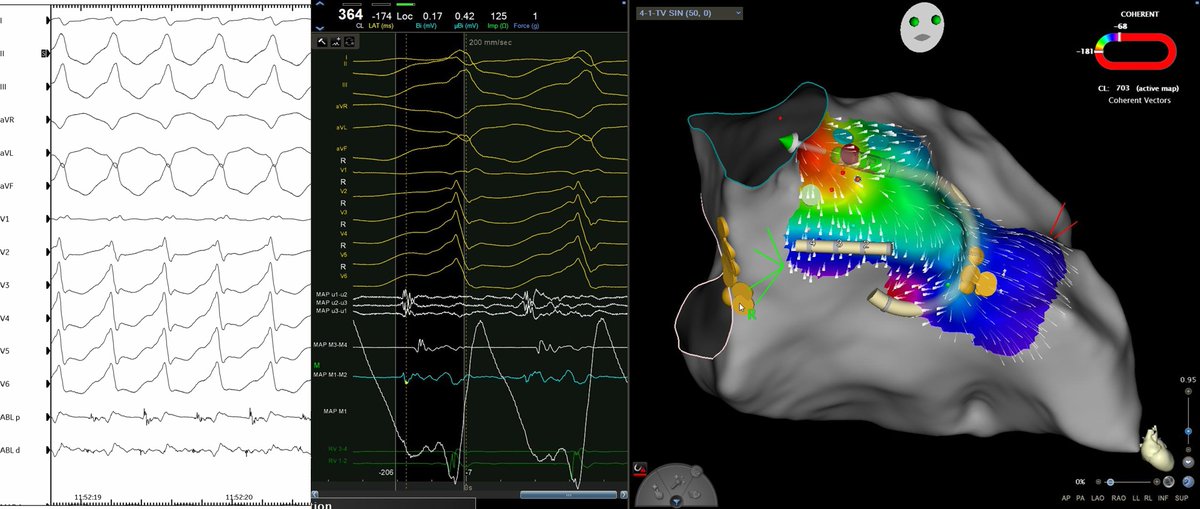

Celebrating 1yr since the publication of our Atlas of ConductSystemPacing #LBBAP #HBP! Thanks @ilpensiero for their support & to the readers for their trust! I hope it has been (& will be) useful to become confident in recognizing #CSP in your procedures! tinyurl.com/CSPAtlas